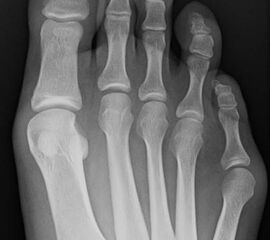

Distale Osteotomien:

Austin Osteotomie nach Chevron (Chevronette)

• Die distale Osteotomie des Os metatarsale V kommt überwiegend bei Typ I und II Deformitäten zu Anwendung.

Diaphysäre Osteotomien:

Diaphysäre Osteotomien kommen vorwiegend bei Typ II Deformitäten zur Anwendung, insbesondere wenn das Zentrum der Achsabweichung im Bereich des diaphysären Knochens liegt. Der Eingriff folgt dem Grundlegenden Prinzip der Orthopädie eine Korrektur möglichst im Zentrum der Deformität durchzuführen 3. Auch bei einer diaphysären Osteotomie erfolgt zusätzlich eine Abtragung der Exostose.